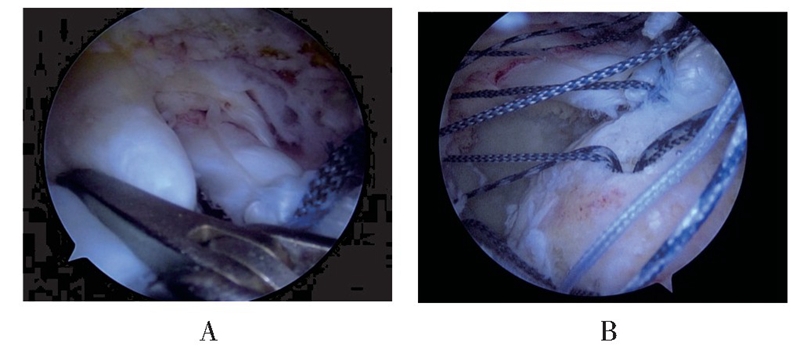

(3)以组织抓钳牵拉后方撕裂肩袖,判断肌腱张力及撕裂形态,在移位固定的LHBT后方植入1~2枚直径4.5 mm Healix带线锚钉(Mitek,双线锚钉),缝合冈下肌腱,然后根据张力情况选择部分或完全修复冈上肌腱,其中缝合固定LHBT的缝线还可用于缝合肩袖组织(见图3)。

图3 组织抓钳牵拉后方撕裂肩袖,判断肌腱张力及撕裂形态(A),在移位固定的LHBT后方植入2枚带线锚钉,连同缝合固定LHBT的缝线一起缝合冈下及部分冈上肌腱(B)